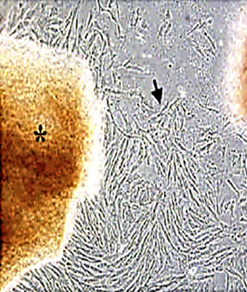

以下圖檔摘錄自”Enhancement of neuroplasticity through upregulation of β1-integrin in human umbilical cord-derived stromal cell implanted stroke model”, Neurobiology of Disease (27), 2007, pp339–353.

高倍顯微鏡下的幹細胞